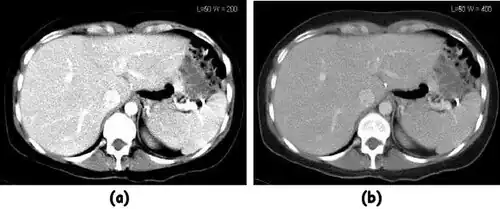

![]() |

- Examples of image display manipulation are shown in the two figures above. In Figure 7.15.2, the same image of a slice through a patient's liver is displayed using a relatively narrow window (high contrast) and also with a wide window. The image with the narrower window appears noisier, but this is merely a reflection of the fact that the gray scale is spread over a narrow range of CT-numbers.